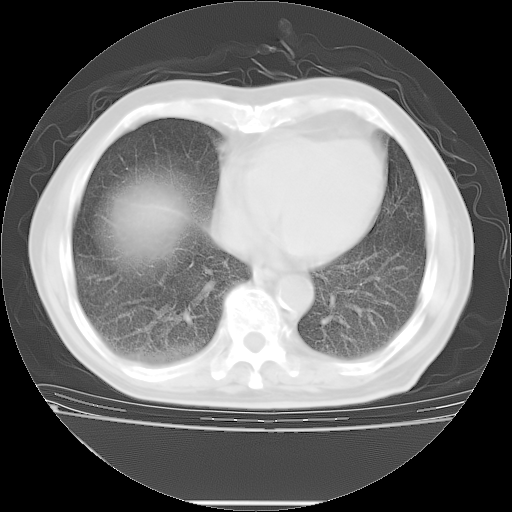

5月9日肺部CT(在4月27日齐鲁医院肺部CT描述部分肺组织磨玻璃样改变,12天后肺组织广泛磨玻璃样改变)

2009年5月9日肺部CT

大致读了系列胸部CT:纵隔窗无明显异常,肺窗:从4、27至今:主要是双肺中下野外带可见毛玻璃样改变,目前处于急性肺泡炎阶段,至于原因考虑1、结替组织或胶原血管性疾病所致?2、恶性疾病如恶组在肺部所致的表现或细支气管肺泡癌?3、药物或其它原因如肺蛋白沉着症所致肺泡炎目前不太可能?总之,明天就去请我院的呼吸科、感染科、血液科和临免专家会诊哈。